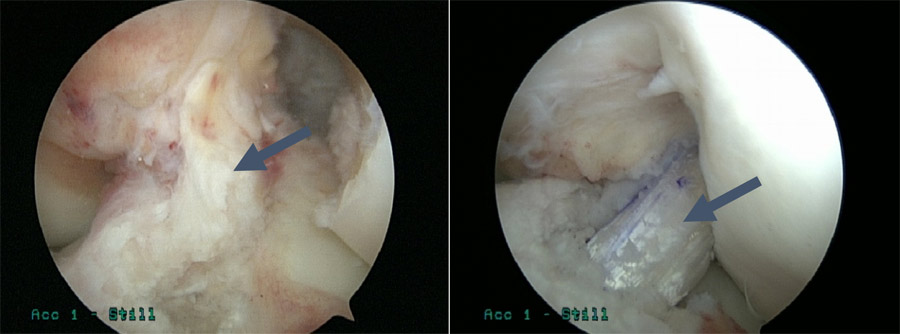

- Dr. Ahmad performs an ACL reconstruction arthroscopically, making two small incisions on both sides of the patella to pass the camera (arthroscope) and other instruments into the joint.

Post-operative X-rays of the tunnels in a patient with bilateral ACL reconstructions done by Dr. Ahmad.

- ACL repairs are performed arthroscopically, where two small incisions are made on both sides of the patella to pass a camera (arthroscope) and other instruments into the joint.

- To repair the ACL, Dr. Ahmad sutures the ligament to the attachment site.